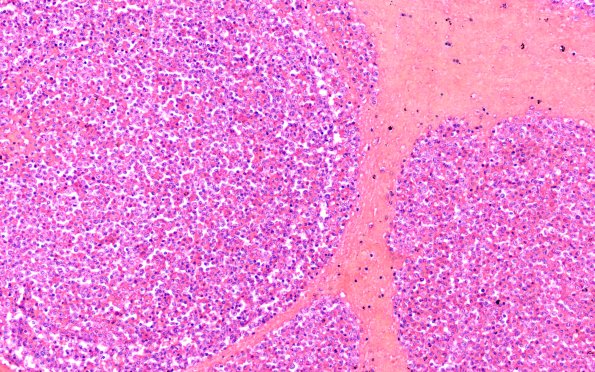

Washington University Experience | NEOPLASMS (HEMATOLYMPHOID) | Granulocytic Sarcoma | 3B6 Leukemic Nodules (Case 3) D 20X

3B6-8 Small hemorrhagic nodules at the periphery of the large frontoparietal hemorrhagic lesion and occasional hemorrhagic nodules in the frontal and occipital cortices were composed of aggregates of myeloblasts, with numerous mitoses, occasional vascular centers and a rim of hemorrhage.